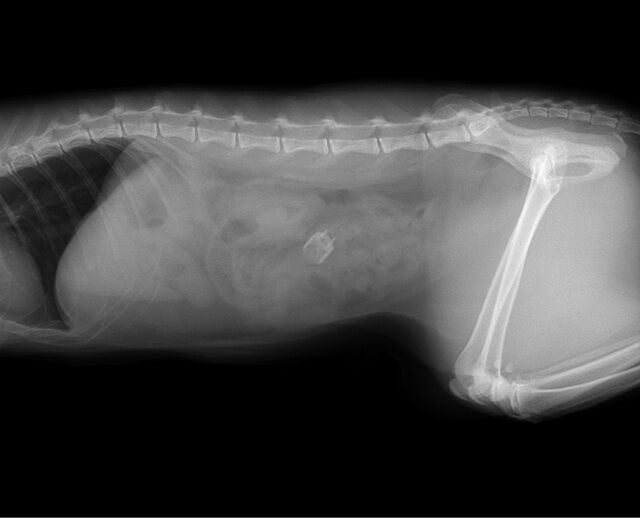

しかし2 、3日後も食欲はなく嘔吐が続いていましたので、レントゲン撮影をしたところ下記のような画像が得られました。

明らかに小腸付近に異物が検出されていましたので、当日に摘出手術を行いました。予想通り小腸にマジックのキャップのようなものが詰まっていましたので、腸を切開し摘出しました。その後は猫ちゃんは二日間入院、点滴し、食欲も戻り元気に退院していきました。